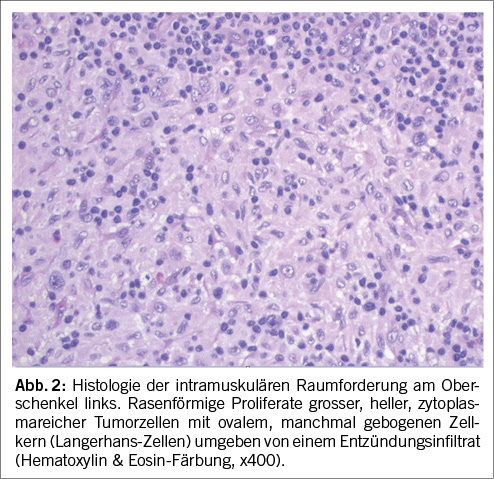

Mittels CT-gesteuerter Biopsie konnte Gewebe perifemoral gewonnen werden. In der histopathologischen Aufarbeitung zeigte sich ein Eosinophilen-reiches Entzündungsinfiltrat mit proliferierten atypischen Zellen mit „Kaffeebohnen-artigen“ Kernen. Die Immunhistochemie mit dem Nachweis der typischen Marker CD1a, Langerin, S100 und CD68 führte zur Diagnose einer LCH (Abb. 2). Somit wurde die Diagnose einer multisystemischen LCH mit Hirn und Weichteilbeteiligung gestellt.

Histopathologisch sind LCH Läsionen durch proliferierte Zytoplasma-reiche Zellen mit Kaffeebohnen-artigem Kern mit häufig länglicher Membranfurchung charakterisiert. Je nach Aktivität der Langerhans-Zell-Histiozytose finden sich beigemischte eosinophile Granulozyten unterschiedlicher Dichte sowie Lymphozyten und Plasmazellen. Die diagnostischen immunohistochemischen Marker für Langerhans-Zellen sind CD1a und Langerin (CD207). Da >50% der LCH eine BRAF pV600E Mutation aufweisen [3], ist auch die BRAF-V600E Immunhistochemie diagnostisch hilfreich. Bei fehlender immunhistochemischer Expression von BRAF, respektive negativer Mutationsanalyse wird meist ein NGS für Gene, welche im MAPK-ERK Signalweg involviert sind, durchgeführt [7].